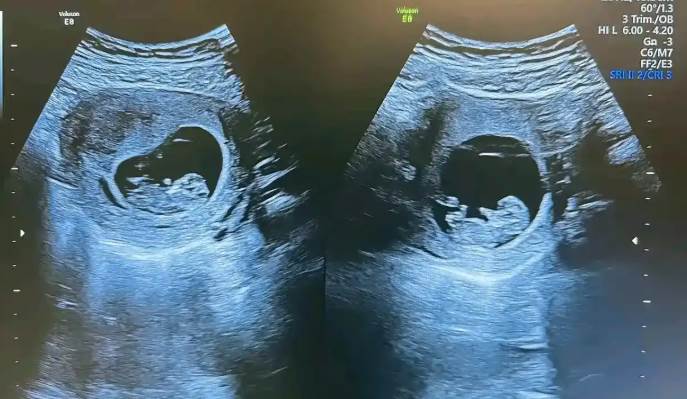

近日國際媒體報導,巴西一名女子在2022年誕下一對雙胞胎,然而在孩子出生八個月後進行親子鑑定時,意外發現兩名新生兒的生父並非同一人。醫學上將此現象稱為 「異父異卵超受精」(Heteropaternal Superfecundation),全球已知案例極少,至今僅約20起,被視為極罕見的自然生理現象。

負責此案的婦產科醫師說明,「異父異卵超受精」可能發生在女性排卵期釋放多顆卵子,並在極短時間內完成受孕,使兩顆卵子受到不同來源的遺傳結合。雖然非常罕見,但在醫學上確實可能存在。

醫師補充,這類雙胞胎會在不同胎盤中發育,整個孕期並無特殊併發症,健康狀況與一般雙胞胎無異。